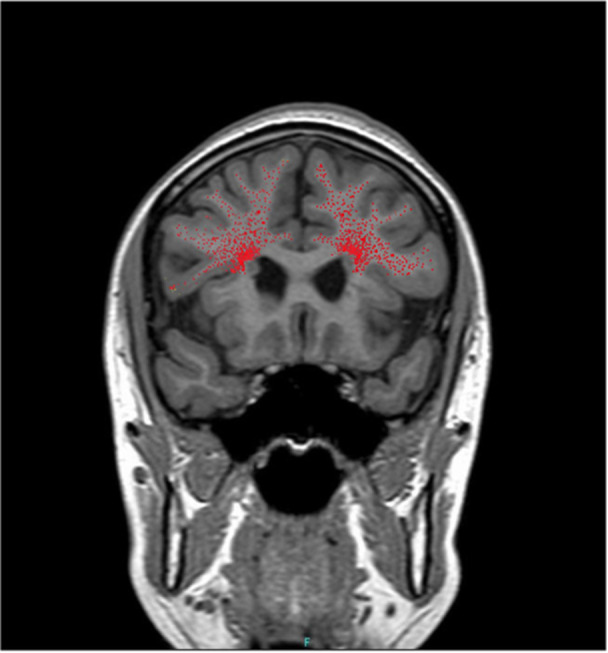

背景:22q11.2缺失综合征与精神分裂症、癫痫发作相关,并常出现抗精神病药物不耐受。脑室周围结节性异位(PNH)是一种神经元迁移障碍,也可在22q11.2缺失综合征患者中观察到。然而,据我们所知,氯氮平在难治性精神分裂症和22q11.2缺失综合征及PNH合并症青少年患者中的应用尚未见报道。病例介绍:一位患有难治性精神分裂症的17岁女性被转介到我院。她表现为幻听,行为混乱,失眠。由于锥体外系症状,多种抗精神病药物、情绪稳定剂、苯二氮卓类药物和改良电休克治疗无效或耐受性差。镇静下进行的脑磁共振成像(MRI)显示PNH。基因检测证实了22q11.2缺失综合征的诊断。开始时密切监测氯氮平,缓慢滴药后症状逐渐改善。大约6个月后出院,临床稳定15个月。结论:脑部核磁共振和基因检测——即使是在镇静状态下进行的——可能是难治性精神分裂症青少年患者有价值的诊断工具。此外,脑结构异常的存在并不妨碍氯氮平的疗效,氯氮平可能仍然是这种情况下可行和有效的治疗选择。

Case presentation: A 17-year-old female with treatment-resistant schizophrenia was referred to our hospital. She presented with auditory hallucinations, disorganized behavior, and insomnia. Multiple antipsychotics, mood stabilizers, benzodiazepines, and modified electroconvulsive therapy were either ineffective or poorly tolerated due to extrapyramidal symptoms. Brain magnetic resonance imaging (MRI) performed under sedation revealed PNH. Genetic testing confirmed a diagnosis of 22q11.2 deletion syndrome. Clozapine was initiated with close monitoring, and her symptoms gradually improved following a slow titration. She was discharged after approximately 6 months and has remained clinically stable for 15 months.